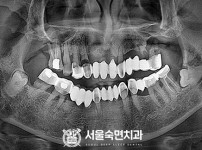

임플란트-전후사진2

치과를-선택할-때-꼭-확인하세요-서울숙면치과-임플란트-전후사진